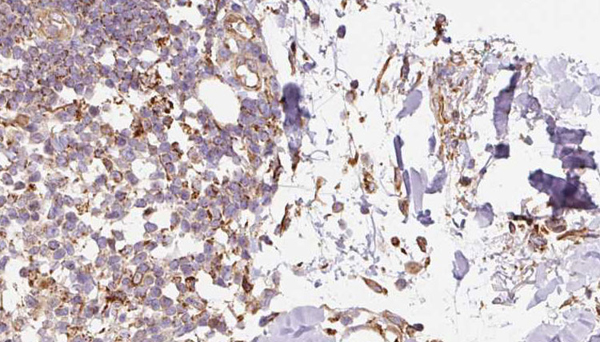

IHC (Immunohistochemistry)

(AAA326162 at 1/100 staining Human Melanoma tissue by IHC-P. The sample was formaldehyde fixed and a heat mediated antigen retrieval step in citrate buffer was performed. The sample was then blocked and incubated with the antibody for 1.5 hours at 22 degree C. An HRP conjugated goat anti-rabbit antibody was used as the secondary.)